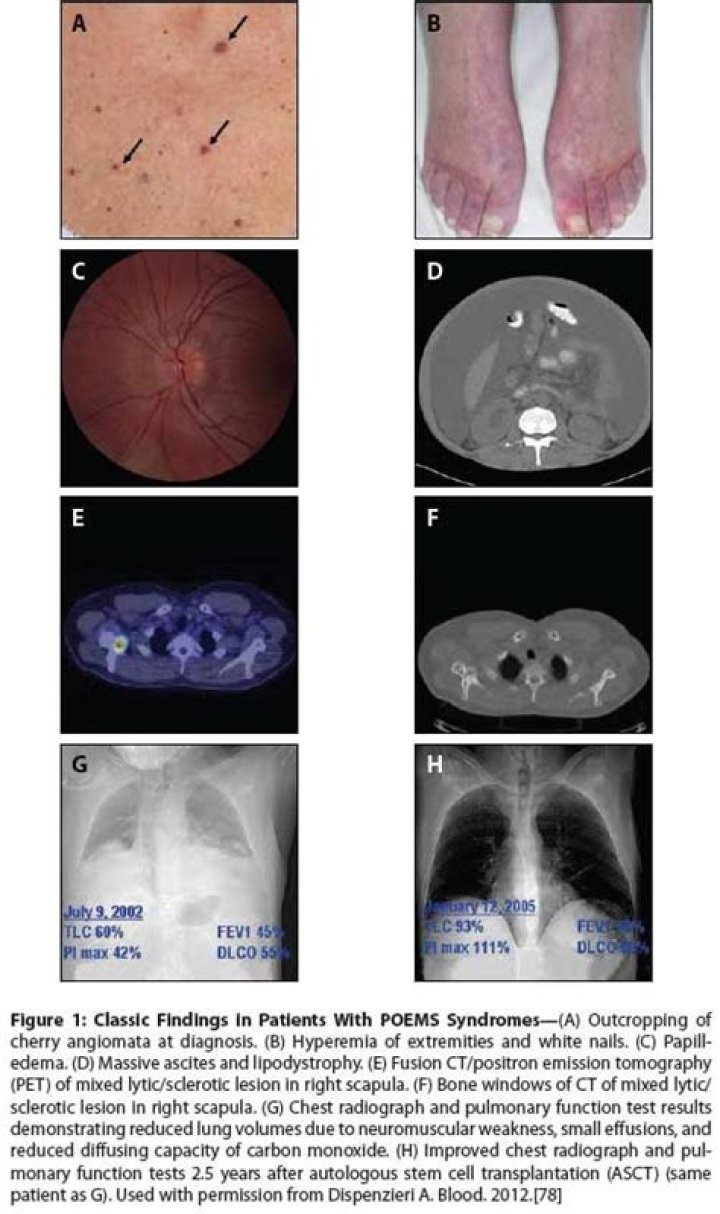

POEMS is an acronym that stands for the disorder's five major signs and symptoms, which include Polyneuropathy, Organomegaly, Endocrinopathy, Monoclonal gammopathy and Skin abnormalities.